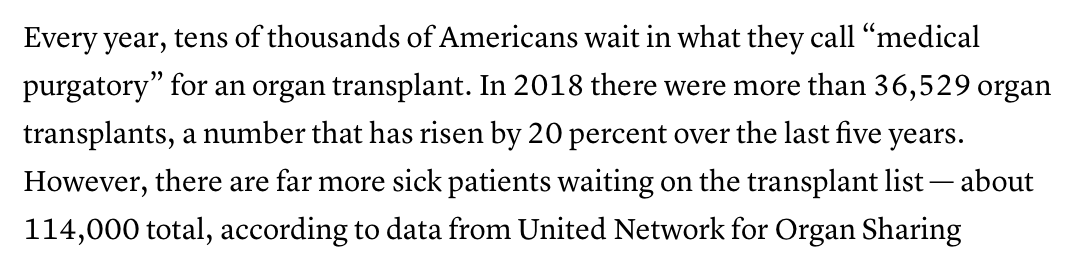

“The idea of solving the human organ shortage with pigs has tantalized surgeons for decades. More than 117,000 Americans are currently on a transplant wait-list in the U.S., according to federal figures, and 22 people die every day awaiting a match.